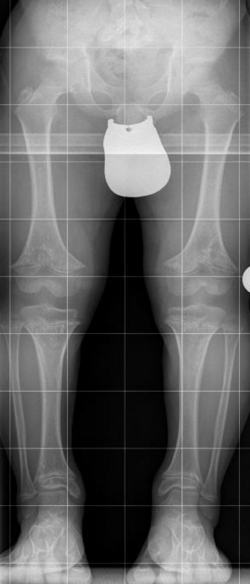

Radiologische Kriterien sind:

- Verbreiterte Metaphysen bei normalen Epiphysen

- Überproportional verkürzter Humerus und Femur

- Schmales Kreuzbein, breite Beckenschaufel mit horizontalem und breitem Pfannendach

- Verschmälerter Abstand der Bogenwurzeln nach kaudal zunehmend, verkürzte Pedikel mit eventueller Spinalstenose, keilförmige Deformierung der Wirbelkörper

- Brachydaktylie mit Dreizackhand[5]

X-ray 10y old male with Achondroplasia | Eigenes Werk | Kinderradiologie Olgahospital Klinikum Stuttgart | Datei:Achondroplasie 10J m.png | |